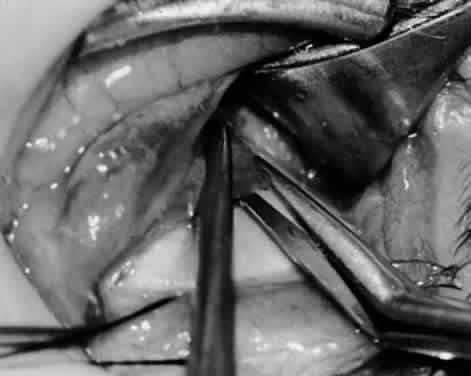

Fig. 7. A Westcott scissor is used gently to open a space beneath the elevated inferior oblique muscle and allow placement of a Green muscle hook.

Fig. 8. The Green muscle hook is placed beneath the belly of the inferior oblique muscle, and the eye is retracted nasally.